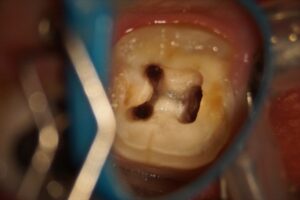

40歳男性の二次虫歯を顕微鏡根管治療